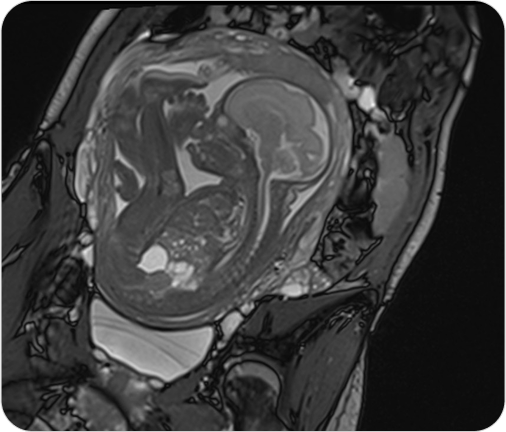

Resonancia Magnética Fetal

La resonancia fetal es un estudio no invasivo que permite observar con gran detalle el desarrollo del bebé en el útero. Es un complemento ideal de la ecografía cuando se necesita información más precisa.

La resonancia magnética fetal permite obtener imágenes detalladas del bebé durante el embarazo, sin utilizar radiación. Se utiliza como complemento del ultrasonido cuando se detectan hallazgos que requieren evaluación más precisa.

¿PARA QUE SE UTILIZA?

- Evaluar el desarrollo del sistema nervioso central fetal (cerebro y médula espinal).

- Detectar malformaciones cerebrales o anomalías estructurales.

- Valorar la anatomía de órganos internos en casos complejos.

- Confirmar o descartar hallazgos dudosos en ecografías.

- Planificar tratamientos o decisiones perinatales junto con el equipo obstétrico.

¿POR QUÉ ES UN ESTUDIO DESTACADO?

- No invasivo y seguro para la madre y el bebé.

- Alta definición de imágenes incluso en embarazos avanzados.

- Permite tomar decisiones médicas informadas y personalizadas.

- Evita resonancias post-natales.

Resonancia Magnética Fetal

La resonancia fetal es un estudio no invasivo que permite observar con gran detalle el desarrollo del bebé en el útero. Es un complemento ideal de la ecografía cuando se necesita información más precisa.

La resonancia magnética fetal permite obtener imágenes detalladas del bebé durante el embarazo, sin utilizar radiación. Se utiliza como complemento del ultrasonido cuando se detectan hallazgos que requieren evaluación más precisa.

¿PARA QUE SE UTILIZA?

- Evaluar el desarrollo del sistema nervioso central fetal (cerebro y médula espinal).

- Detectar malformaciones cerebrales o anomalías estructurales.

- Valorar la anatomía de órganos internos en casos complejos.

- Confirmar o descartar hallazgos dudosos en ecografías.

- Planificar tratamientos o decisiones perinatales junto con el equipo obstétrico.

¿POR QUÉ ES UN ESTUDIO DESTACADO?

- No invasivo y seguro para la madre y el bebé.

- Alta definición de imágenes incluso en embarazos avanzados.

- Permite tomar decisiones médicas informadas y personalizadas.

- Evita resonancias post-natales.